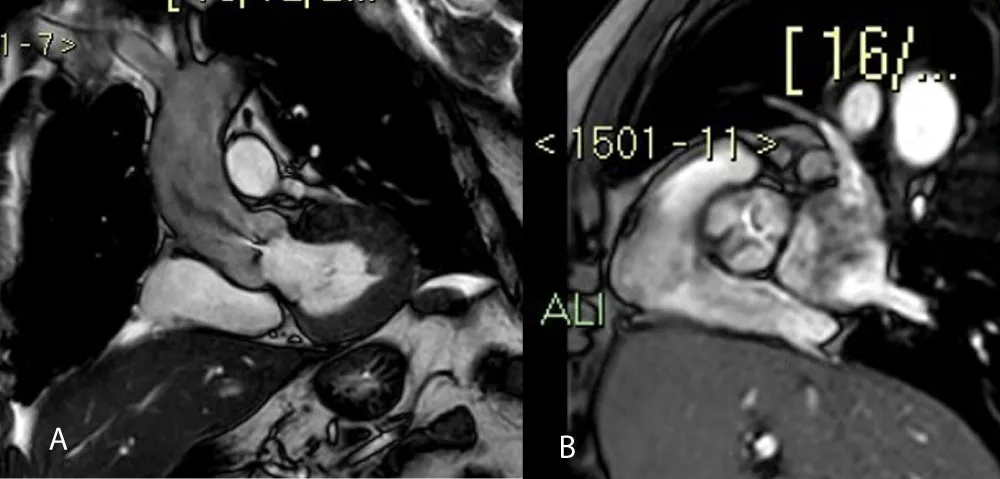

GLS was calculated offline with images obtained from apical windows 4, 3, and 2 chambers. The software automatically calculated the degree of longitudinal deformation. The myocardial was divided into six zones (inferior, infero-septal, antero-septal, anterior, antero-lateral, infero-lateral). The average strain profile of the wall was analyzed for each area. From this analysis, we obtained the systolic peak of longitudinal strain (PSLS: Peak Systolic Longitudinal Strain) which is the maximum negative value of deformation during the ejection phase. The GLS was calculated from the averages of the values obtained by the individual myocardial walls for each window (Figure 1). 2D imaging was used for the calculation of the LVM. The formula for determining the mass was LVM = Area x Height. The area was calculated from the parasternal short-axis window (at the level of the papillary muscles) by subtracting the ventricular cavity from the area calculated at the epicardium level. The height was measured from the 4-chamber window as a base-apex distance. The ventricular mass was also indexed according to the formula LVMi = LVM/BSA. According to the guidelines, the upper reference value was 88 g/m2 in women and 102 g/m2 in men.

Download Image

Figure 1: Bull-eyes of 17 segments, calculating GLS (A) and CW doppler through the aortic valve, which shows severe aortic stenosis (B).